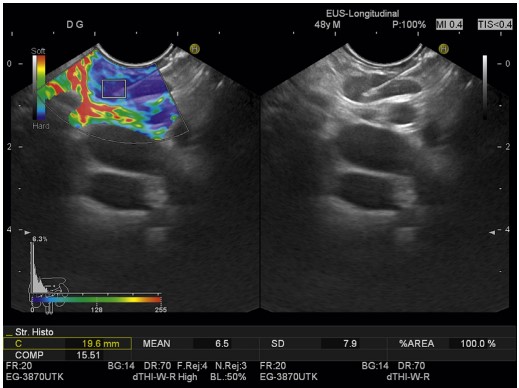

Real-Time EUS Elastography

Real-time EUS elastography offers qualitative and semiquantitative insights into tissue stiffness. This technology is particularly beneficial in distinguishing between benign and malignant tumors, providing a non-invasive approach to evaluating lesions.